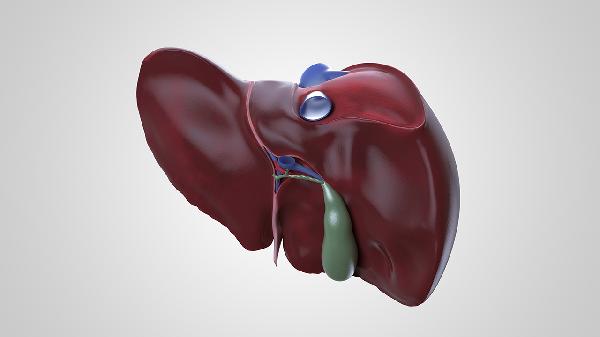

肝脾肿大可致腹部膨隆,叩诊呈浊音。门静脉高压时可能出现腹水,表现为肚脐外凸或腹壁静脉曲张。腹胀常伴有触痛感,婴幼儿会因不适而哭闹不安。